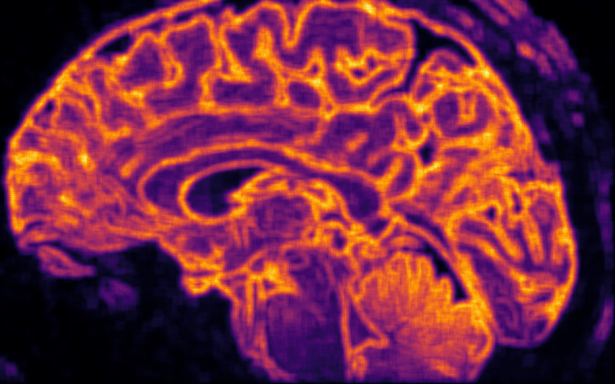

Médical

Voir n’est plus regarder : c’est comprendre la structure du monde cellulaire.

Loin du contraste classique, ϕ explore la richesse interne des tissus.

Elle distingue l’homogène du structuré, le bruit du sens, et redonne au regard médical une dimension topologique : celle de l’information vivante.

Les structures fines, souvent invisibles à l’œil nu, s’y dessinent comme des reliefs entropiques — un paysage du corps, révélé par la mathématique du vivant.